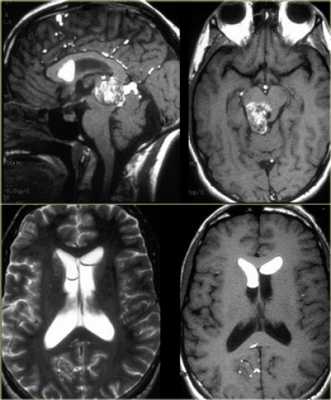

Классификация

- Кисты шишковидной железы

- Полость (киста) промежуточного паруса (лат. Cavum veli interpositi)

- Арахноидальная киста

- Пинеоцитома

- Пинеобластома

- Смешанные опухоли шишковидной железы

- Сосочковая опухоль шишковидной железы

- Герминома

- Тератома

- Хориокарцинома

- Эмбриональная карцинома

- Карцинома желточного мешка

- Смешанные герминативноклеточные опухоли

- Астроцитома

- Менингиома (около шишковидной железы)

- Метастазирование шишковидной железы

- Мальформация вены Галена

- Тромбоз внутренней мозговой вены

- a — Опухоль с преимущественной локализацией в четверохолмной цистерне с диаметром узла до 2,5 см — 10%

- b — Опухоль с преимущественным расположением в задних отделах III желудочка с диаметром узла до 2,5 см — 12%

- c — Опухоль средних размеров (комбинация вариантов 1 и 2) с диаметром опухолевого узла до 4 см — 32%

- d — Опухоль больших размеров, полностью занимающая четверохолмную цистерну и задние отделы III желудочка, нередко врастающая в один из боковых желудочков; максимальный размер 6-7 см — 41%

- e — Гигантская опухоль, практически полностью занимающая полость III желудочка, часть IV желудочка и врастающая в оба боковых желудочка; диаметр более 7 см — 5%

![3]()

Пример менингиомы, локализующаяся рядом с шишковидной железой.

![4]()

Пример типичного дермоида

![5]()

![6]()

Пример герминомы. Обратите внимание на гомогенное контрастирование и обызвествления.